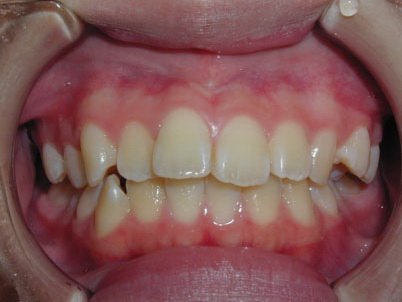

上顎前歯部のガタガタを気にして来院されました。上顎の左右第一小臼歯 (4番目の歯) を抜歯し、マルチブラケット装置で治療しました。治療期間は2年3か月でした。

初診時

終了時